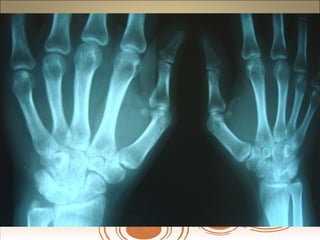

Achados radiográficosAchados radiográficos

 Osteopenia peri-articularOsteopenia peri-articular

 Diminuição do espaço articularDiminuição do espaço articular

 Presença de cisto e erosõesPresença de cisto e erosões

 Edema de partes molesEdema de partes moles

 Presença de deformidadesPresença de deformidades

1- osteopenia 2-erosões 3-sub-luxação